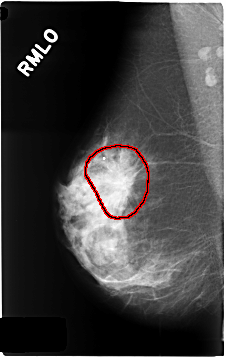

C_0339_1.RIGHT_MLO

FILE: C_0339_1.RIGHT_MLO.OVERLAY

TOTAL_ABNORMALITIES 1

ABNORMALITY 1

LESION_TYPE MASS SHAPE IRREGULAR MARGINS SPICULATED

ASSESSMENT 5

SUBTLETY 5

PATHOLOGY MALIGNANT

TOTAL_OUTLINES 1

BOUNDARY